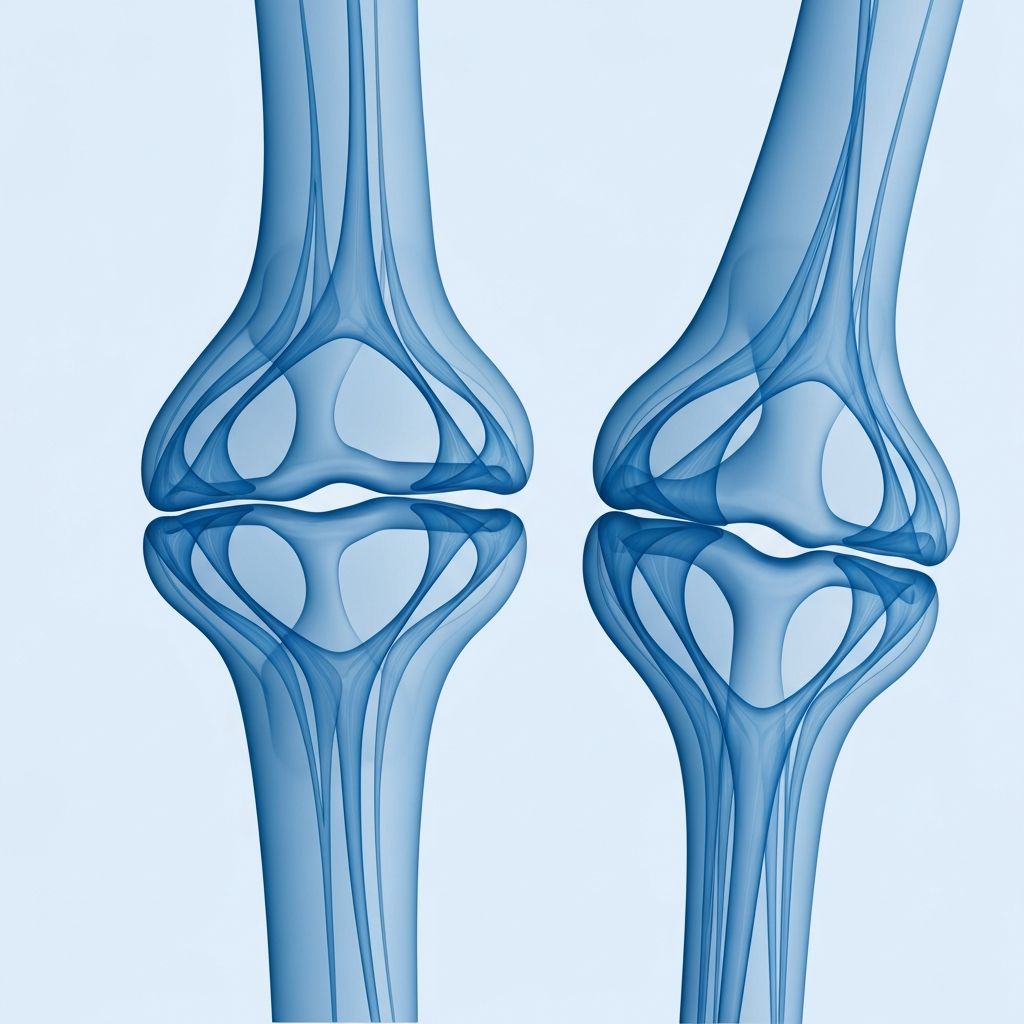

Visualizing Joint Anatomy: An Interactive Overview

A comprehensive understanding of joint anatomy requires familiarity with several key structures and their functions. The skeleton provides the rigid framework, while joints serve as articulation points enabling movement. Bones meet at joints, where specialized tissues and fluids facilitate smooth motion.

The synovial joint represents the most complex and mobile joint type, featuring a sophisticated architecture: articular cartilage covers the bone ends, synovial fluid provides lubrication, the joint capsule provides containment, and supporting ligaments and muscles provide stability and movement capability. Understanding this anatomical organization provides context for comprehending how various nutrients and compounds support these structures in maintaining their function.